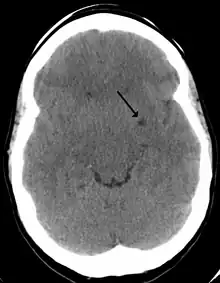

Son una estructuras fisiológicas en el parénquima cerebral normal.[2] Consisten en espacios perivasculares que rodean a las arterias perforantes del cerebro, y se debe pensar siempre en ellos al visualizar estructuras quísticas en la sustancia blanca del cerebro y ganglios basales, redondeadas o alargadas, siguiendo el trayecto de los vasos perforantes.[5]Se pueden observar a través de una resonancia magnética cerebral.[5] Allí las características morfológicas de imagen de los espacios de Virchow-Robin son áreas redondas o tubulares, de bordes suaves.[2]

En ocasiones pueden crecer y convertirse en gigantes espacios de Virchow-Robin.[4]Al agrandarse y convertirse en espacios gigantes de Virchow-Robin producen un efecto de masa que puede traer diversos síntomas neurológicos.[1]En casos anormales se relacionan con diversas patologías neurológicas neurodegenerativas, como la enfermedad de Alzheimer, las enfermedades cerebrovasculares y las lesiones cerebrales traumáticas,[2]ictus, esclerosis múltiple, angiopatía amiloidea cerebral,[6] e hidrocefalia.[3]Incluso se ha descrito un caso de neuralgia del trigémino secundaria a los espacios de Virchow-Robin gigantes en el área dorsal pontino.[1]